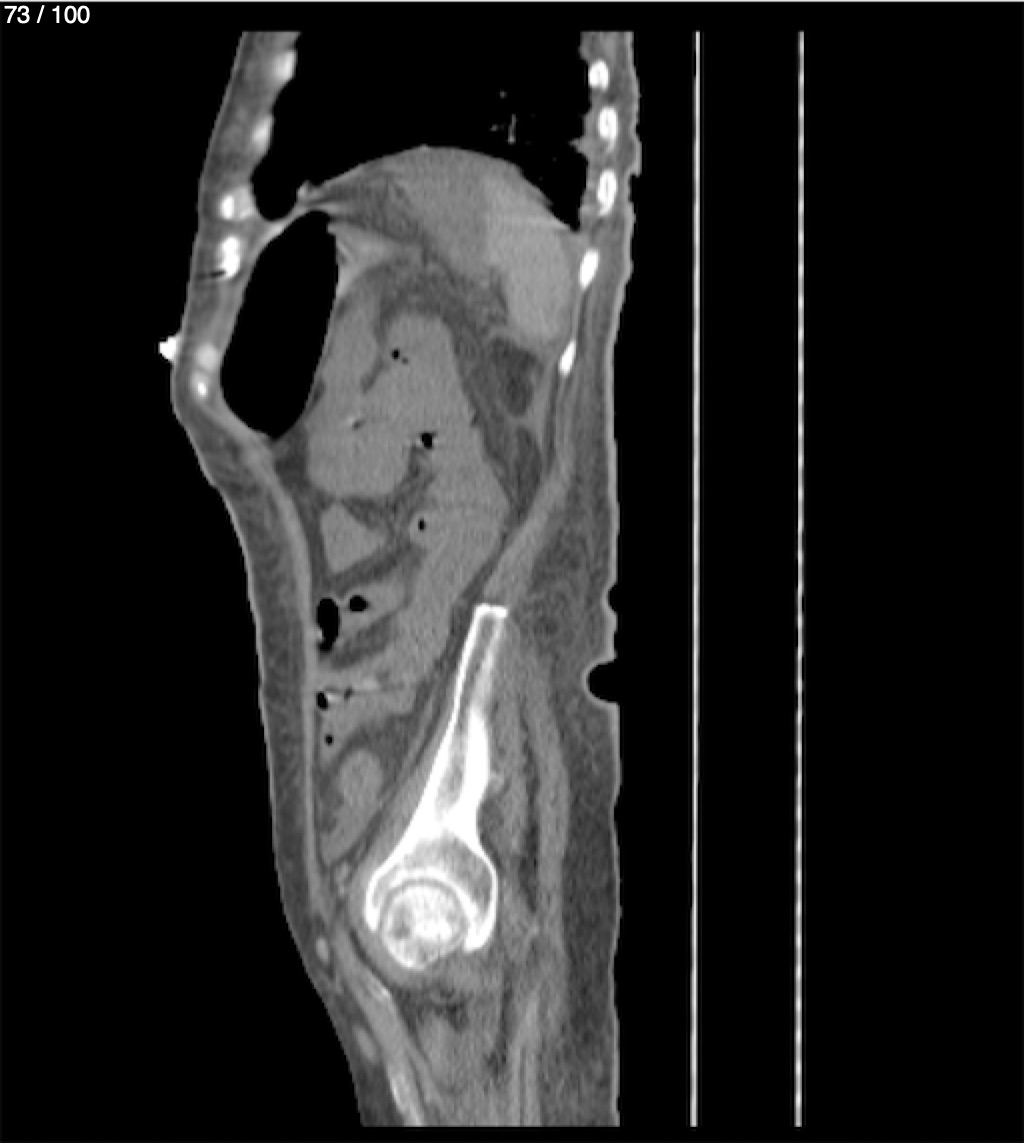

Hilda Geronimo Mendez 60A - T.C Abdomen Simple